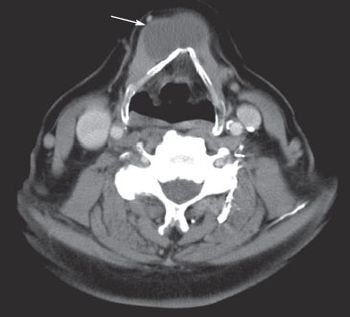

Thyroglossal duct cyst; HCV-HIV coinfection; slurred speech and trouble swallowing and chewing . . . see how well you do on the quiz questions this week.